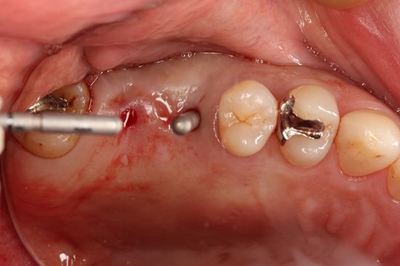

まずは安全な深度までドリリングして確認します。

深度ゲージを挿入した状態でレントゲンを撮影します。

角度は想定どおりで安堵します。

ここからはソケットリフトを行いますのでオステオトームで上顎洞を挙上します。

オステオトームでのソケットリフトを終えました。

正確な位置でインプラント床を拡大するために粘膜剥離をせずに行います。

骨の柔らかい方向へオステオトームが逃げますので粘膜をガイドにして

拡大していきます。

骨の上部は必ずドリルで形成します。

この時点で粘膜剥離して骨の状態を確認します。

深度ゲージで確認します。